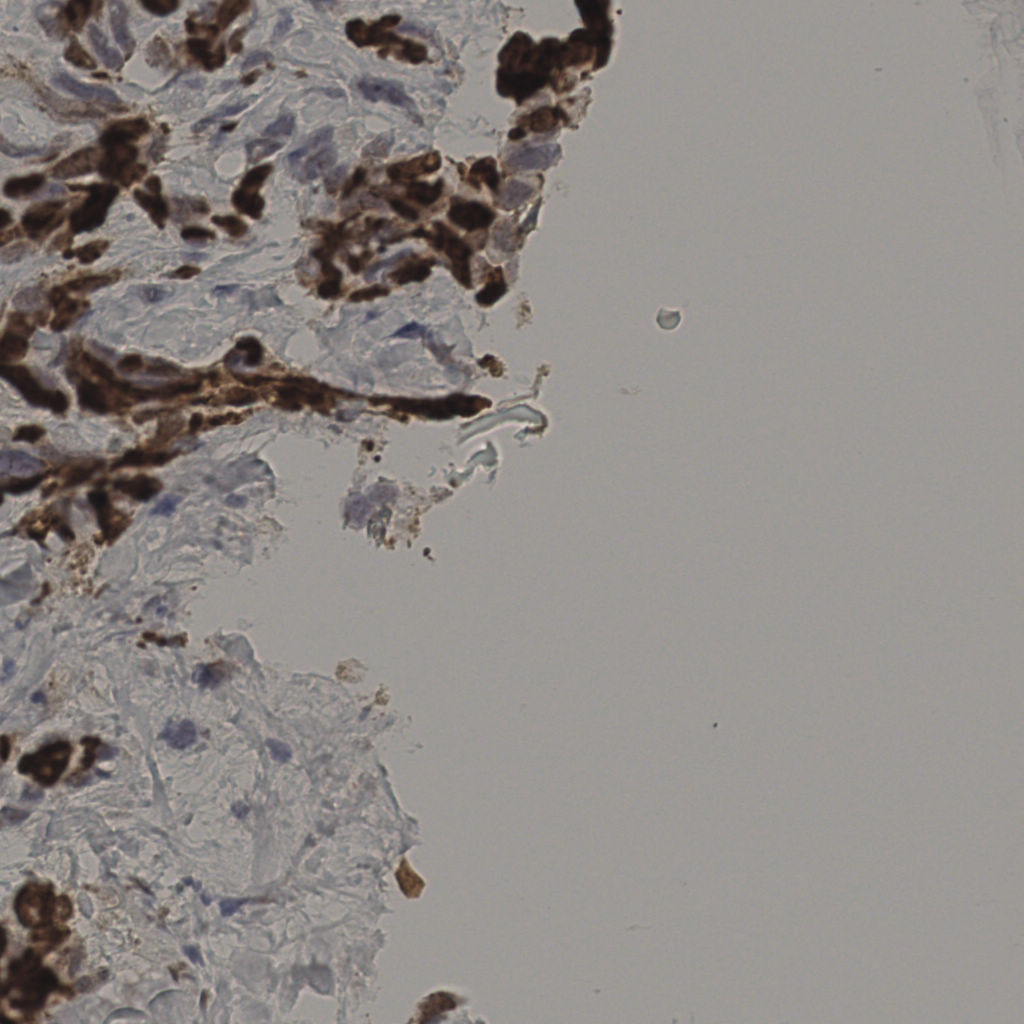

17.75%

Ki67 指数

阴 7986

阳 1723

切片统计

总切片

2640

有效

412

已标记

412

有效率

16%